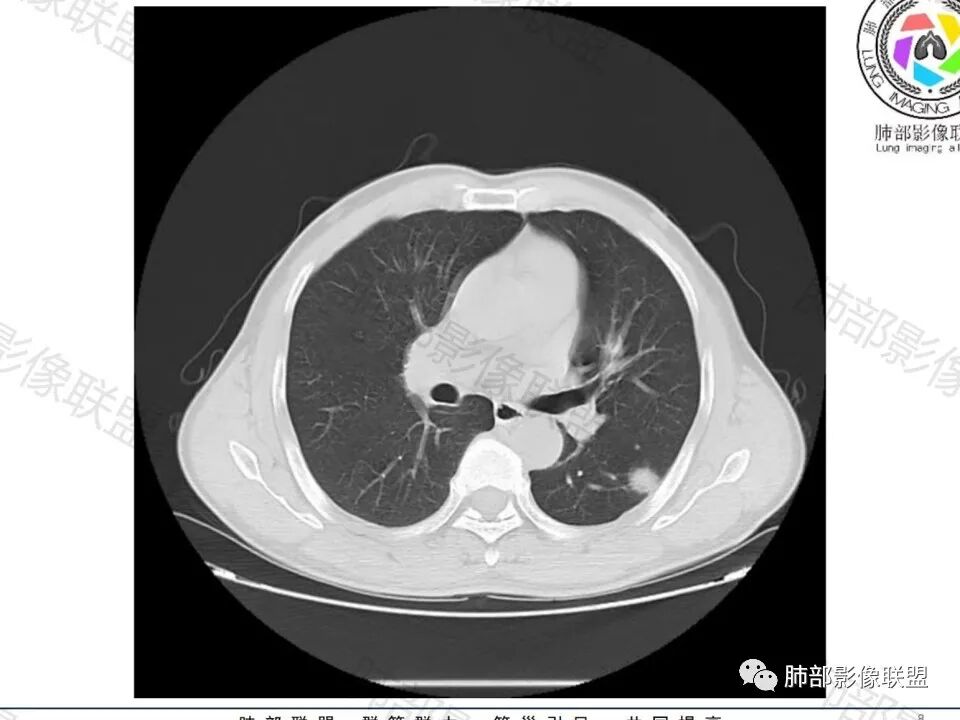

男,60体检发现左肺下叶结节,左肺下叶类圆形结节影,边界清晰,边缘见浅分叶及细短毛刺,病灶内见增粗血管影穿行,相应层面胸膜增厚,双肺另见微小结节影,增强扫描病灶轻度强化,考虑隐球菌,除外腺癌。

左肺下叶胸膜下实性小结节,边缘可见毛刺,轻度收缩,近端与血管束相连,远端轻度牵拉胸膜,并远端可见小空泡,平扫密度均匀,增强后渐近性强化,考虑腺癌,鉴别隐球菌

老年男性,CT左肺下叶胸膜下类圆形结节,边缘光滑,无分叶,可见毛刺,相邻胸膜多条牵拉,局部胸膜增厚,(多见炎性病变),病灶周围可见模糊晕征,血管支气管进入,考虑隐球菌,现实中万万不能排除肺癌。

中老年男性患者,无症状体检发现,胸部CT:左下肺内前基底段近胸膜下类圆形结节,边缘清晰,周围晕征,周围毛刺细软,有胸膜牵拉及血管进入,增强扫描明显不均匀强化,考虑炎性肉芽肿,隐球菌可能,鉴别腺癌

老年男性,查体发现,左肺下叶靠近胸膜下结节,边缘膨隆,胸膜牵拉,有细软毛刺,周围有空泡征?中度强化,有血管进入,收缩力不强感觉,我也考虑隐球菌,鉴别肺癌,粘液腺癌?

晨读:左肺下叶胸膜下实性小结节,边缘可见模糊晕及毛刺,轻度收缩,与支气管关系不清,近端与血管束相连,内见小空泡,平扫密度均匀,均匀强化。远近可见多个小结节。考虑炎性肉芽肿,隐球菌病,鉴别结核、腺癌。

类圆形,边缘稍平直,周围晕中细微毛刺,密度均匀,均匀强化,血管走形自然,稍牵拉扭曲,支气管在近端堵塞

结节周围有磨玻璃影,边界似清不清的,但是总体不如炎性晕征那么模糊;

有收缩力,但是很轻,按照常理,实性结节因为有占位效应,不太会有收缩力,但是叶间胸膜有凹陷。所以讲,这个结节还是开了放心。